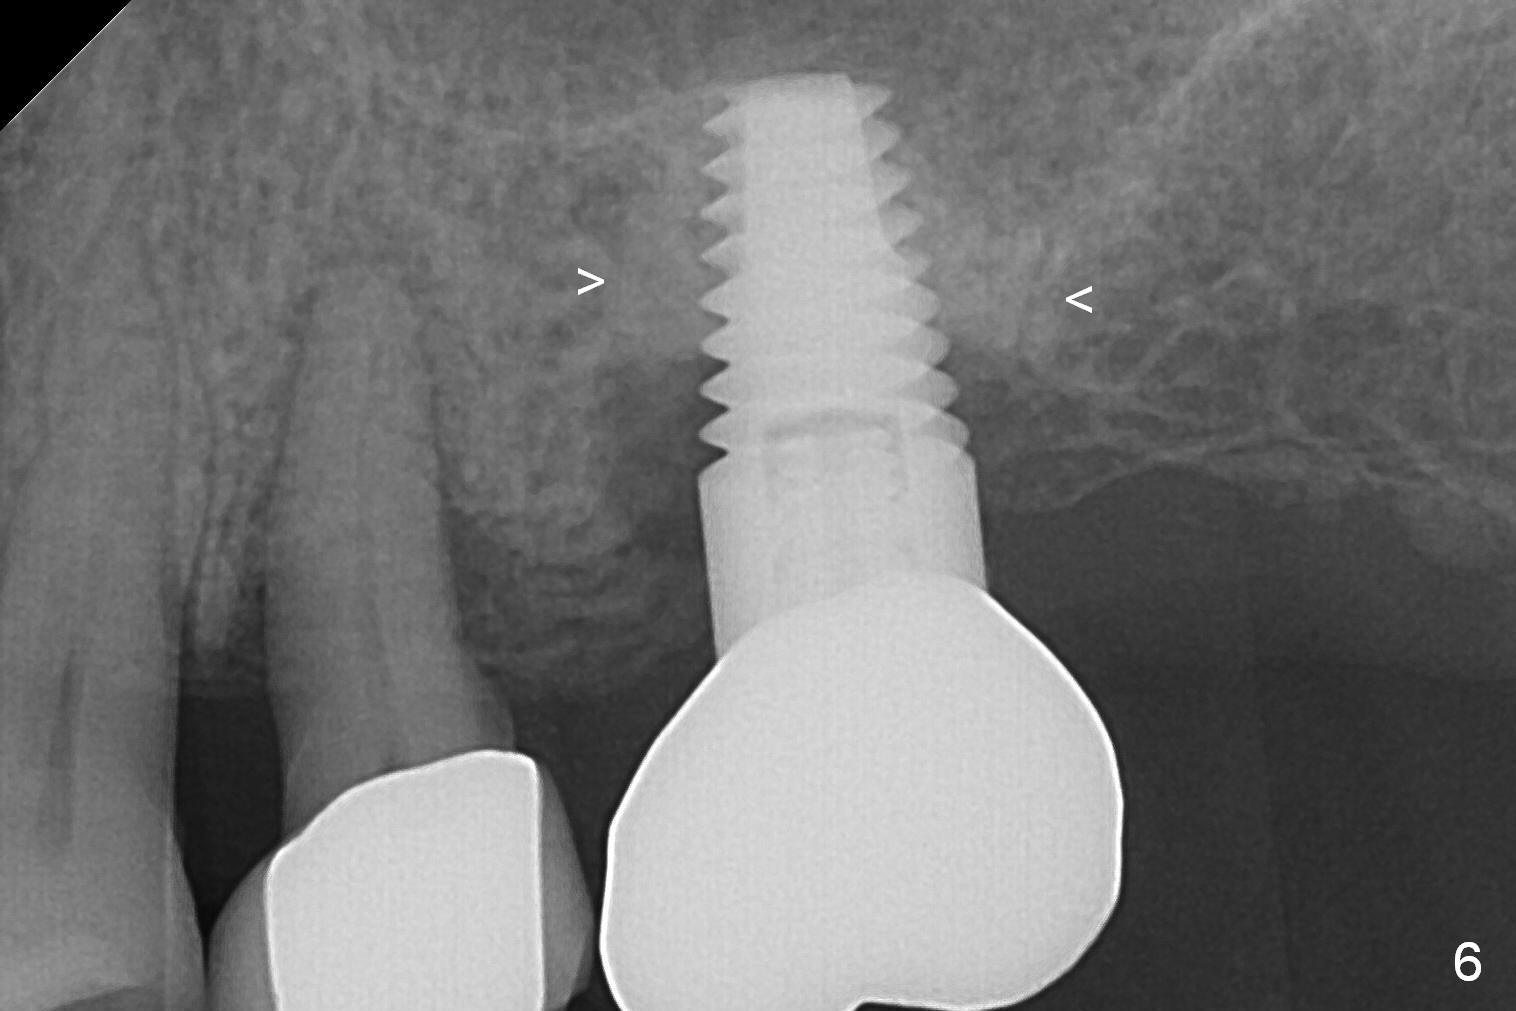

A 73-year-old woman is a possible bruxer with partial edentulism; the tooth #13 had increased periodontal ligament (pdl) space 4 years ago (Fig.1 *). A 5x14 mm tissue-level implant is placed at the site of #14 (Fig.2). The implant appears to be osteointegrated in 6 months (Fig.3). There is crestal bone loss 8 months post cementation (Fig.4 *). The persistent increased pdl at #13 is most likely associated with occlusal tramua from the tooth #19 (Fig.5 (13 months post cementation of #14)). Three years post #14 cementation, the tooth #13 has mobililty II (Fig.6); bone density increases around the apical half of the implant (arrowheads). Normally bone density is the highest coronally where functionality dictates. This indicates the bone loss is getting worse at #14 as well.